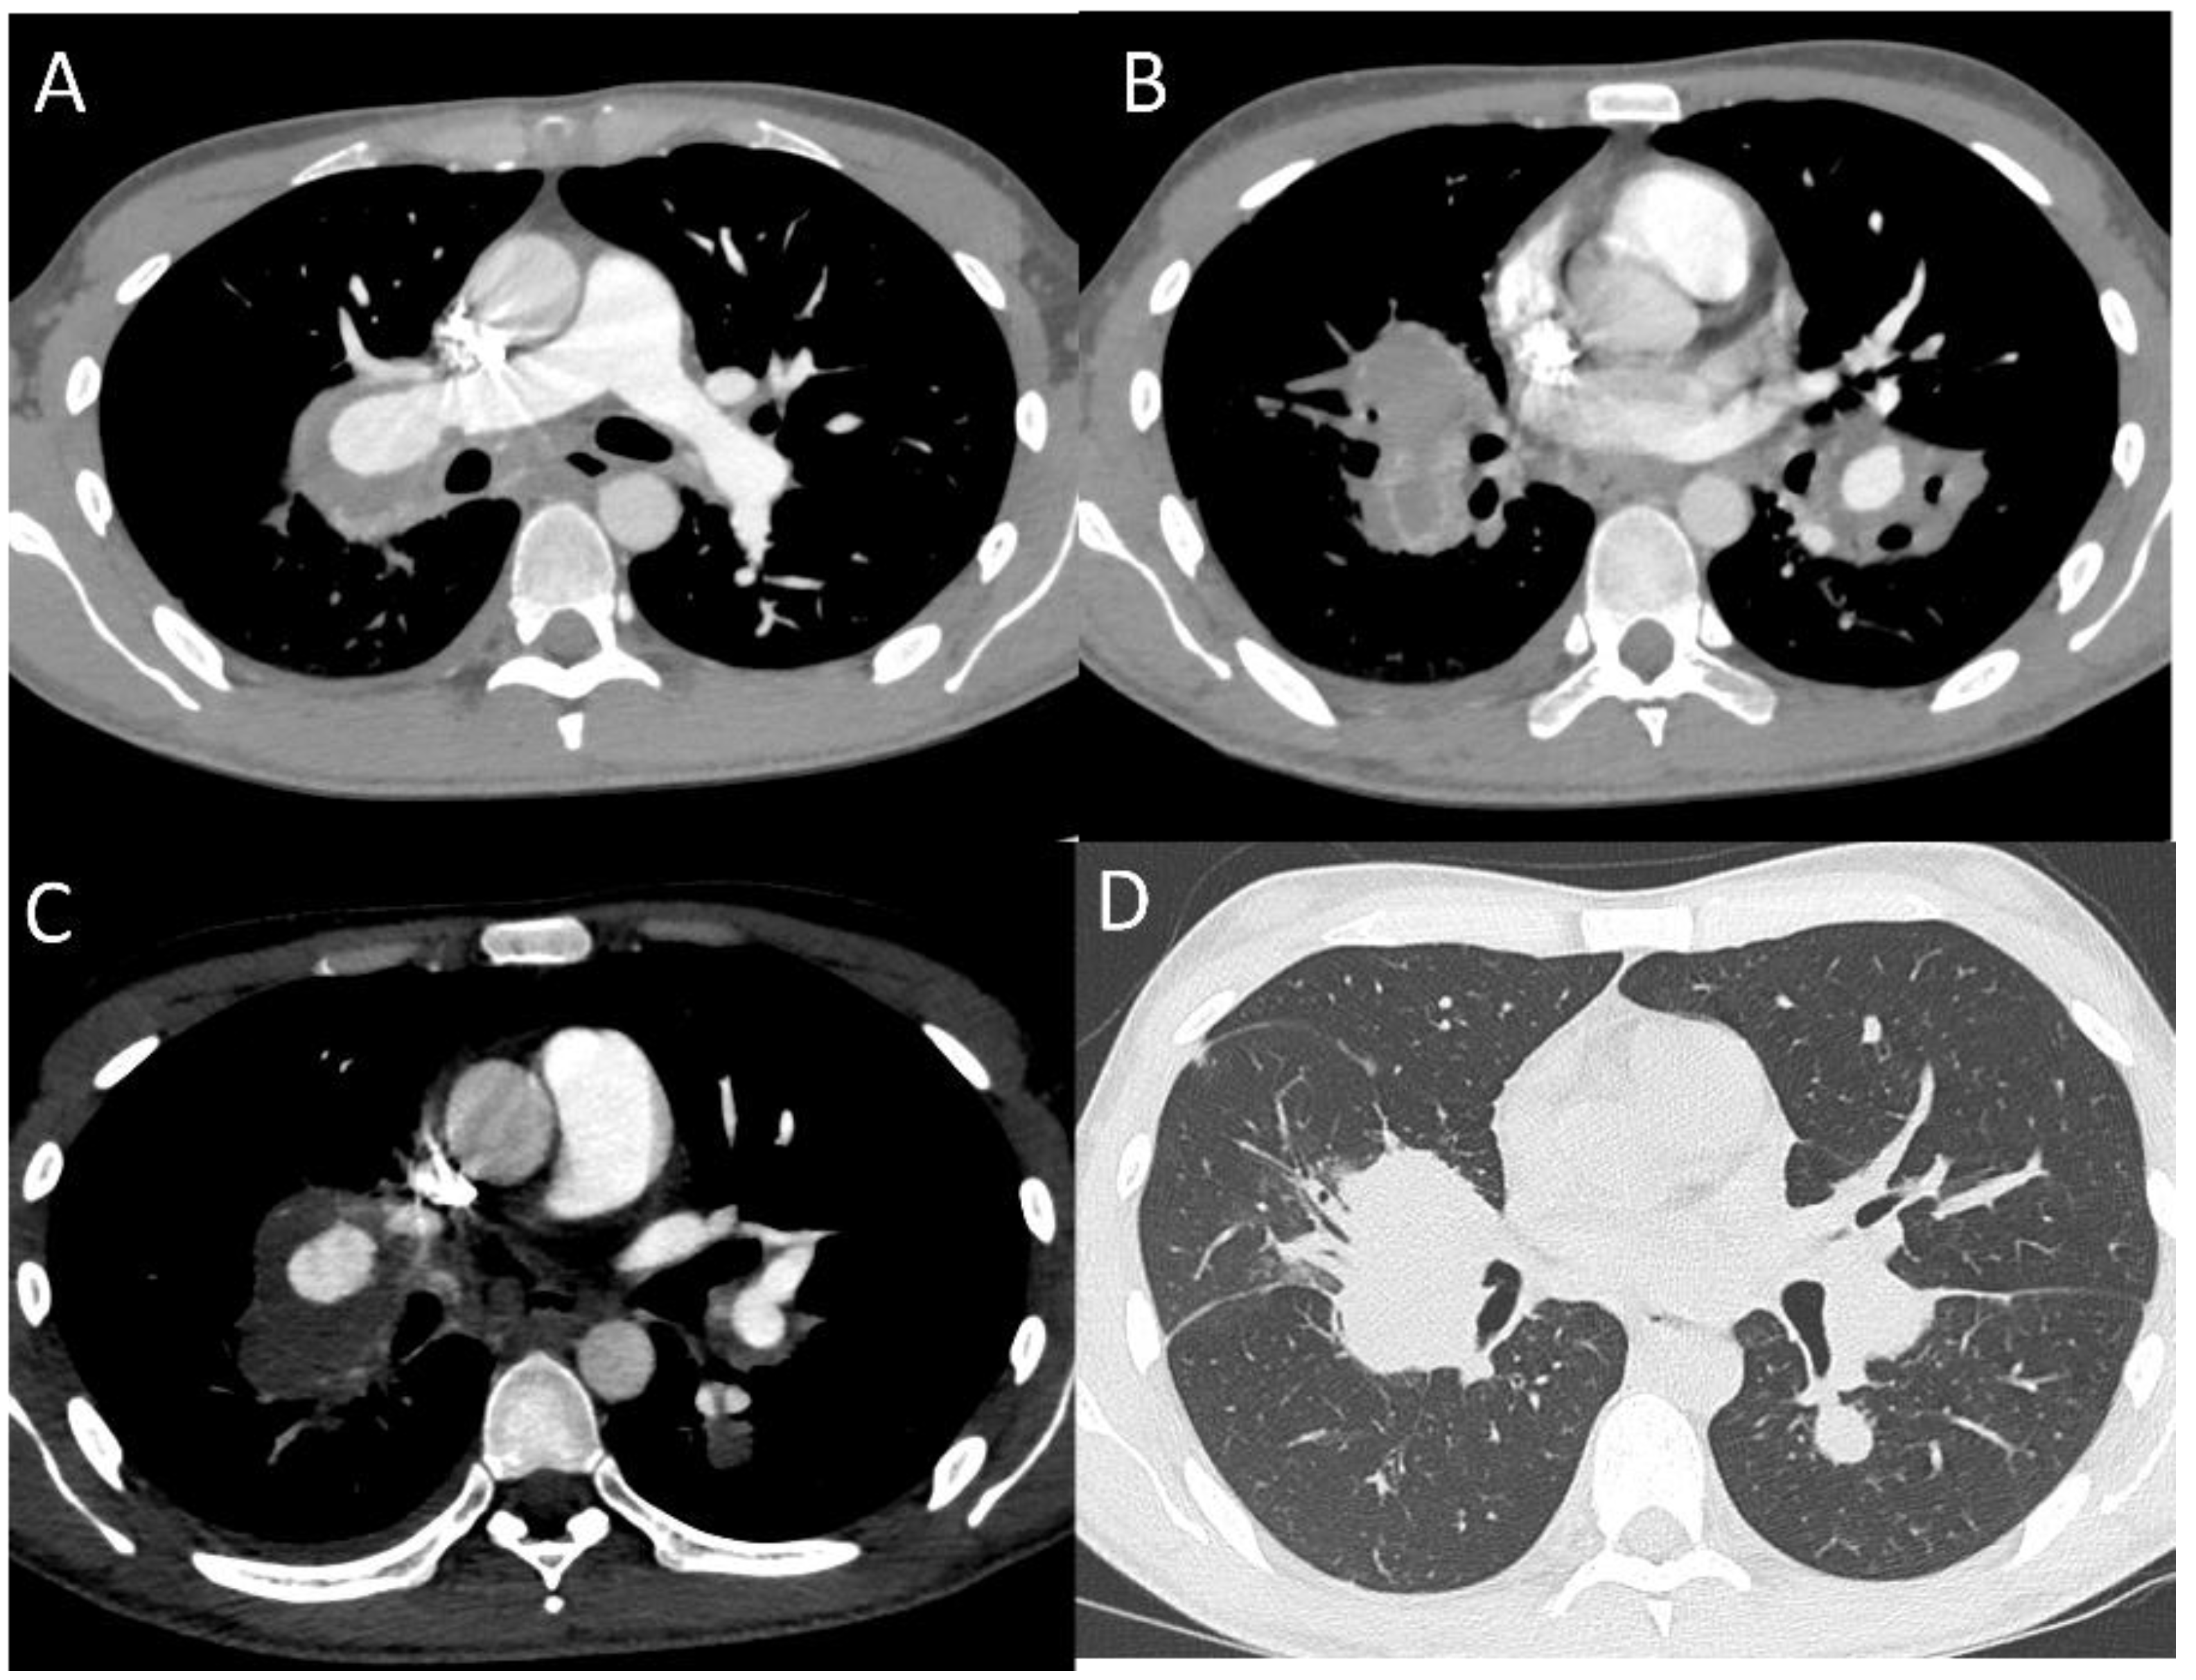

2.1.2. Pulmonary Arterial Manifestations

- Hiller, N.; Lieberman, S.; Chajek-Shaul, T.; Bar-Ziv, J.; Shaham, D. Thoracic Manifestations of Behçet Disease at CT. Radiographics 2004, 24, 801–808. [Google Scholar] [CrossRef]

- Emad, Y.; Abdel-Razek, N.; Gheita, T.; El-Wakd, M.; Gohary, T.; Samadoni, A. Multislice CT Pulmonary Findings in Behçet’s Disease (Report of 16 Cases). Clin. Rheumatol. 2007, 26, 879–884. [Google Scholar] [CrossRef] [PubMed]

- Chae, E.J.; Do, K.H.; Seo, J.B.; Park, S.H.; Kang, J.W.; Jang, Y.M.; Lee, J.S.; Song, J.W.; Song, K.S.; Lee, J.H.; et al. Radiologic and Clinical Findings of Behçet Disease: Comprehensive Review of Multisystemic Involvement. Radiographics 2008, 28, 1–56. [Google Scholar] [CrossRef]

- Ceylan, N.; Bayraktaroglu, S.; Erturk, S.M.; Savas, R.; Alper, H. Pulmonary and Vascular Manifestations of Behcet Disease: Imaging Findings. AJR Am. J. Roentgenol. 2010, 194, W158–W164. [Google Scholar] [CrossRef]